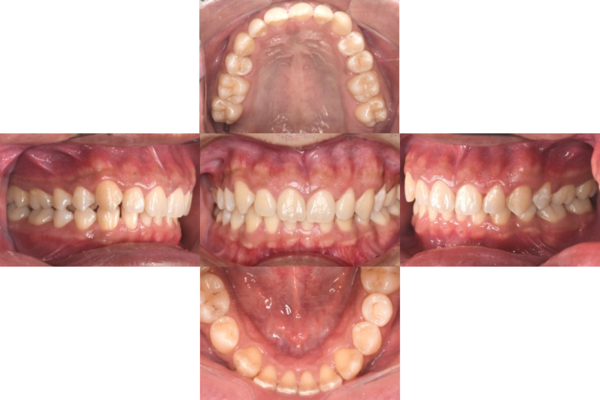

症例5

before

症例

after

歯周病検査(治療前)

歯周病検査(治療後)

レントゲン写真

基本情報

年齢・性別 32歳・男性

主訴 主訴:歯ぐきから出血する

治療部位:全顎

治療内容 「全顎」

歯周基本治療(歯周精密検査、スケーリング、OHI、SRP)

治療期間 約3ヶ月

治療費 歯周基本検査:約600円(保険診療3割負担)

スケーリング、OHI:約2,000円(保険診療3割負担)×2回

SRP、OHI:約1,500円(保険診療3割負担)×4回

歯周精密検査:約1,200円(保険診療3割負担)×2回

合計金額13,000円

(2025年2月現在)

治療方針 ①検査

レントゲン、口腔内写真を撮影して、歯や歯周組織の状態を確認します。

また、歯周病の検査で歯周ポケットの深さや出血の有無を確認します。

②スケーリング、OHI(口腔衛生指導)

スケーリングをして歯の表面の歯石を除去します。

また、正しい歯磨きの仕方や、フロスの通し方を一緒に確認します。

③歯周精密検査

前回歯石除去と歯磨き指導を行なった結果、歯ぐきの状態がどれぐらい改善したか検査します。

④SRP

歯ぐきの内側についてる歯石を除去します。

⑤歯周精密検査

SRP後、歯周病が改善されたか、検査します。

歯周ポケットが4ミリ以上の部位は、再度SRPを行います。

今回は歯周病の状態が安定したため、3ヶ月おきの定期検診で歯周病の再発や進行を防ぎます。

特記事項 歯周精密検査について:

・歯周ポケットが4ミリ以上ある場合は歯周病で、3ミリ以下は健康な歯ぐきです。

・出血の有無で炎症があるか確認します。

・磨き残しがある部分を確認して記録します。

担当者所見 初診時は、写真を見て分かるように、歯ぐきが赤く腫れていました。

また、歯周病の検査では、全体的に歯と歯の間の部分の歯周ポケットが4ミリあり、全体の約81%から出血が認められました。

出血量も多く、歯ぐきに触れた瞬間に出血しました。

レントゲンで骨のレベルがしっかりとあることが確認できました。

そのため、ご自身で正しい歯磨きを継続することで改善すると考えました。

歯周基本治療を経て、再度検査した結果、歯周ポケットはほぼ3ミリ以下に改善しました。左下7番の残存した歯周ポケットは、隣の親知らずを抜いたため経過観察します。

出血率は約4%まで改善し、出血量も点状で少なくなりました。

今後は右上2番、右下3番の歯ぐきの発赤の改善と、出血率0%を目指して、定期検診でメンテナンスしていきます。